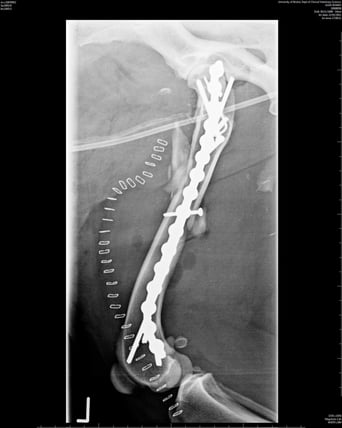

Buttress or bridging

This is when the fracture fragments cannot be aligned. An IM pin is often driven through the furthest ends of the fracture to help align the fragments and then a plate is placed with screws in the proximal and distal parts of the fracture with the main part of the plate acting as a bridge across the gap where the fragments are. This helps to maintain alignment of the limb. Used alone in this way, the plate would be exposed to bending forces which is why it is often used alongside an IM pin as this will counteract these forces. Used in this way, the plate and pin will take on the load, giving the bone time to heal ( Figure 4; Conzemius and Swainson, 1999). The size of the plate and screws used will be determined by the surgeon based on preoperative radiographs. The size of the plate will determine the size of the screws; for example, a 2.0mm plate will always require 2.0mm screws, a 3.5mm plate will require 3.5mm screws, and so on.

The size of the plate and screws used will be determined by the surgeon based on preoperative radiographs